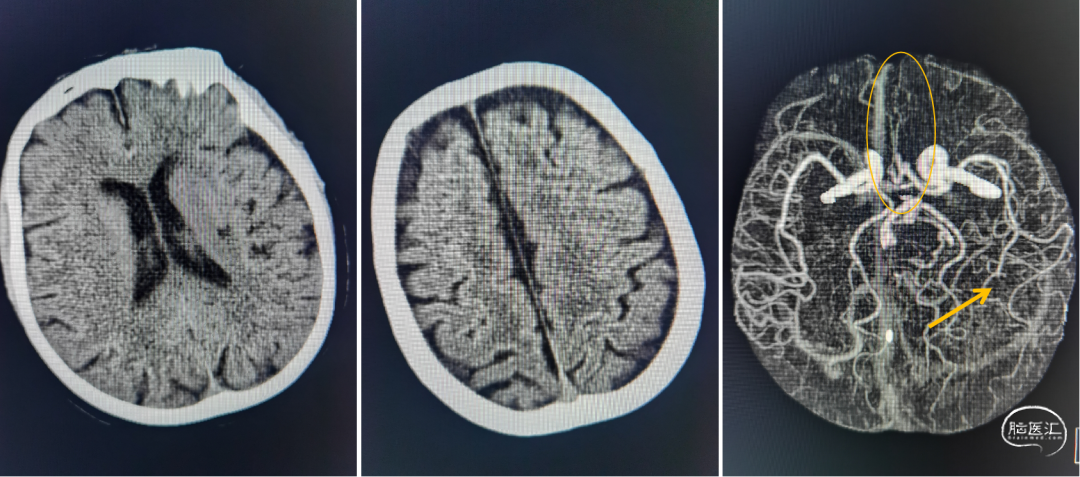

急诊头部CT未见出血、左侧侧室旁见陈旧性梗死病灶;头部CTA:双侧大脑前动脉均由左侧发出、双侧大脑前动脉栓塞可能、左侧大脑前动脉起始处小动脉瘤、左侧大脑中动脉下干远端栓塞。